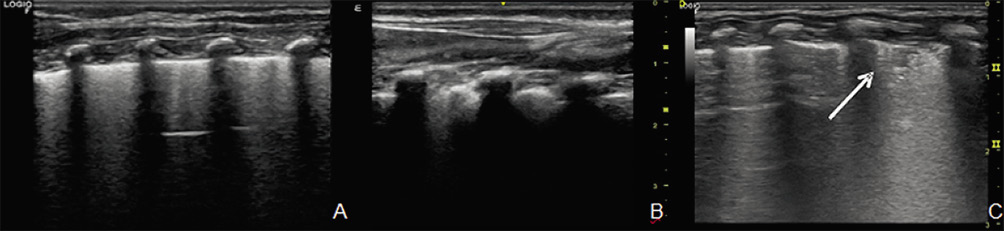

– Pequeñas consolidaciones subpleurales: las áreas de hipoventilación pulmonar con ausencia de aire alveolar se visualizan en forma de consolidaciones adyacentes a la línea pleural (Fig. 8).

Figura 8. Patrones ecográficos en bronquiolitis. A. Aumento de líneas B difusas, múltiples/coalescentes. B. Engrosamiento o irregularidad pleural. C. Pequeñas consolidaciones subpleurales (flecha).

En la bronquiolitis es típica la afectación bilateral y heterogénea, que alterna áreas de pulmón patológico con áreas de pulmón sanas, que lo diferencia de otras entidades que también pueden presentar un síndrome intersticial, como son el edema cardiogénico, la neumonía intersticial o el síndrome de distrés respiratorio agudo.